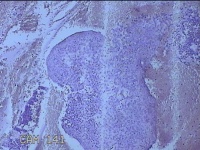

宫颈组织

性别

女

年龄

39岁

临床诊断

人乳头瘤病毒感染

一般病史

宫颈癌筛查异常。

标本名称

大体所见

灰白暗红色不规则碎组织2.2x1.8x0.3cm一堆。